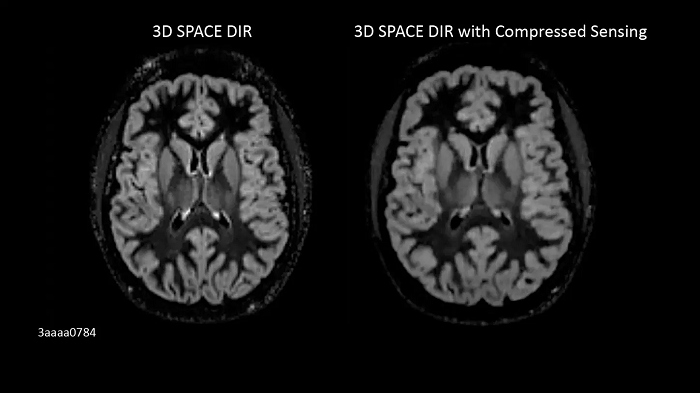

3D CS SPACE DIR

Isotropic 3D imaging of the brain with Compressed Sensing within just 3 minutes per scan.

Left:

3D SPACE DIR | PAT 2 | 1.4 mm iso | TA 6:07 minutes

Right:

3D CS SPACE DIR | CS 7 | 1.0 × 1.0 × 1.0 mm3 (interpolated) | TA 3:07 min (interpolated) | TA 3:07 minutes

Image Credit: Siemens Healthineers